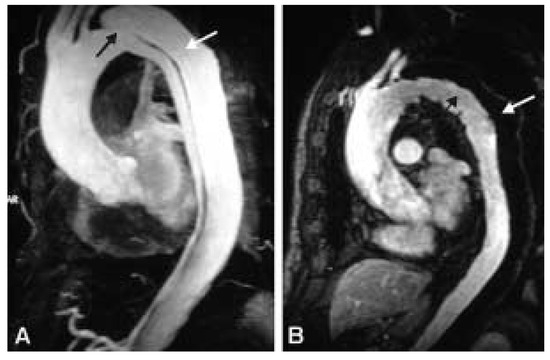

Une patiente de 31 ans souffrant d’une cardiopathie congénitale consulte car elle souhaite une grossesse [...]